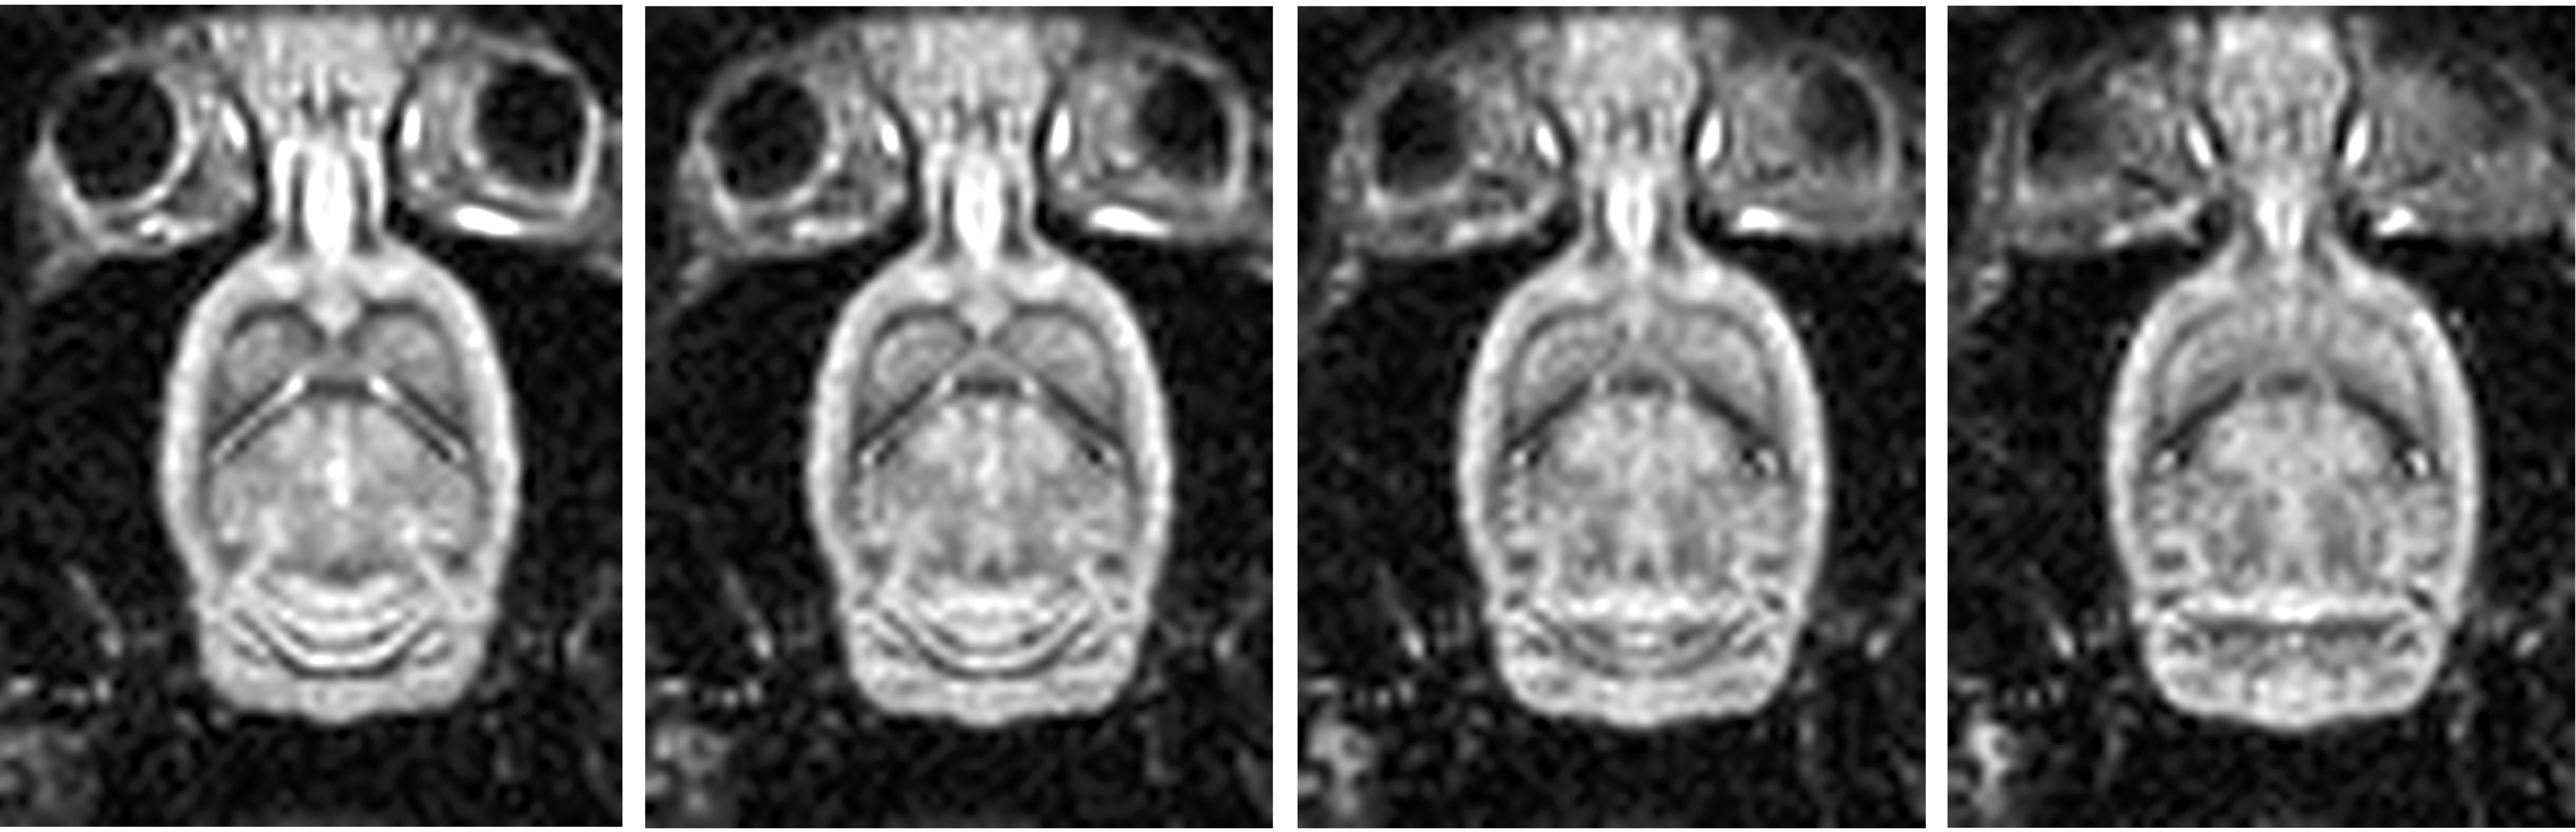

• in vivo imaging of small animal models including mice, rats, and certain amphibians

Hyperpolarization is a technology that enhances the signal from tracer molecules by a factor of 10,000-100,000.  This makes it possible to image the transport, uptake, and metabolism of dilute tracer molecular and metabolites with MRI.  Pyruvate (seen in images above) is a common metabolic probe used to assess rates of glycolytic fermentation in cancer through its conversion to lactate.  In the images above, a tumor-bearing mouse (left) shows high levels of pyruvate signal (center) in the large vessels, while high rates of lactate formation are seen within the tumor (right).